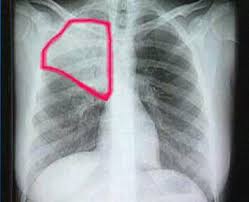

Día Mundial contra la Neumonía:12 de Noviembre

Su objetivo es sensibilizar a la opiniòn pública respecto de los graves problemas de salud pùblica que genera esta enfermedad ,sobre todo en la poblaciòn infantil y que genera muchas muertes evitables.

La Neumonía mata más niños que el Sida ,la malaria y el sarampión combinados en todo el mundo,sin embargo,(la Neumonìa),no está con fuerza en la agenda de quienes toman decisiones.